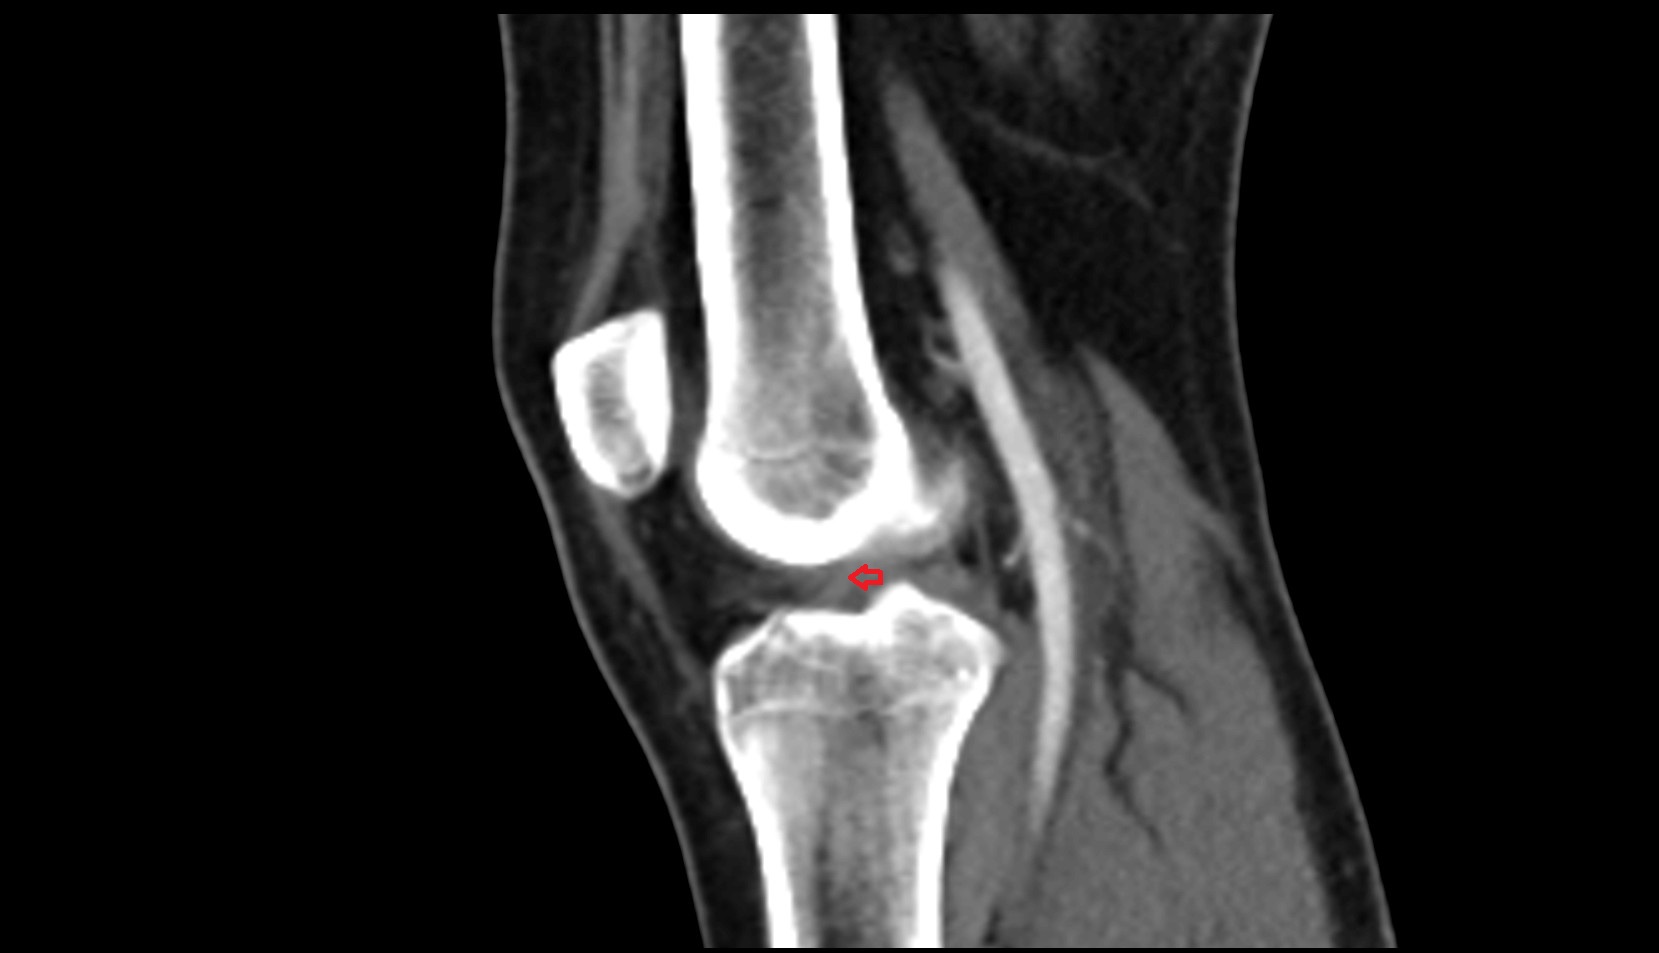

- Medial epicondyle of femur

- Lateral epicondyle of femur

- Lateral condyle of femur

- Medial condyle of femur

- Tibia

- Fibula

- Knee Joint